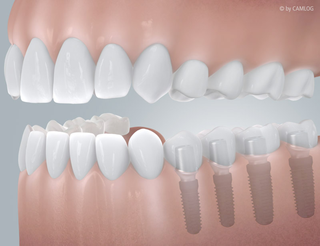

OH JE, EIN ZAHN FEHLT

Schnell kann es gehen!

Ein Unfall beim Sport oder ein Sturz im Alltag und plötzlich fehlt ein Zahn. Implantate sind hier eine schnelle und einfache Lösung – “naturnah” und unsichtbar. Fühlt sich an wie Ihr natürlicher Zahn und funktioniert auch genau so. Die kleinen und leistungsstarken Titan-Schrauben von Camlog übernehmen die Aufgaben Ihrer ursprünglichen Zahnwurzel. Darauf wird Ihre neue individuelle Zahnkrone befestigt. So ist alles wieder an seinem Platz – ganz natürlich, als wäre nichts gewesen.

Sind Implantate einmal eingesetzt, nehmen sie genau die Position Ihres natürlichen Zahns ein. Insbesondere auch da, wo es nicht direkt sichtbar wird: Camlog Implantate sind der natürlichen Zahnwurzel nachempfunden. So werden Knochen und Zahnfleisch richtig belastet und ausgeformt. Gesunde Zähne bleiben grundsätzlich unberührt und müssen nicht wie bei einer festsitzenden Brücke abgeschliffen werden. Es sind auch keine Metallklammern um benachbarte Zähne als zusätzliche Befestigung nötig, wie beispielsweise bei herausnehmbaren Teilprothesen. Bei Implantaten ist all dies überflüssig – eben rundum eine gelungene Lösung.

Befund

Auffällige Zahnlücke: Nach Zahnverlust

Versorgung

Lückenlos versorgt, mit einem Implantat